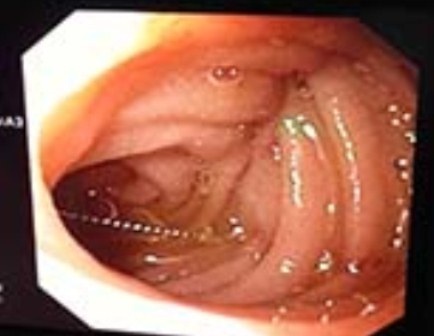

Sau khi hội ý nhanh, các bác sĩ tại bệnh viện Nhi Đồng 1 quyết định thực hiện cuộc nội soi cấp cứu để gắp dị vật ra ngoài. BS. Nguyễn Phúc Thịnh cho biết: “Ống nội soi tìm kiếm khắp dạ dày nhưng không phát hiện cây kim, chúng tôi quyết định kiểm tra tới tá tràng. Phải tìm đến tận tá tràng D4 mới phát hiện cây kim đang nằm ngang, đầu nhọn chuẩn bị xuyên qua thành ruột. Sau nhiều nỗ lực và thận trọng di chuyển, cây kim cuối cùng cũng được đưa ra ngoài, tránh cho bệnh nhi phải bước vào một ca mổ lớn”.